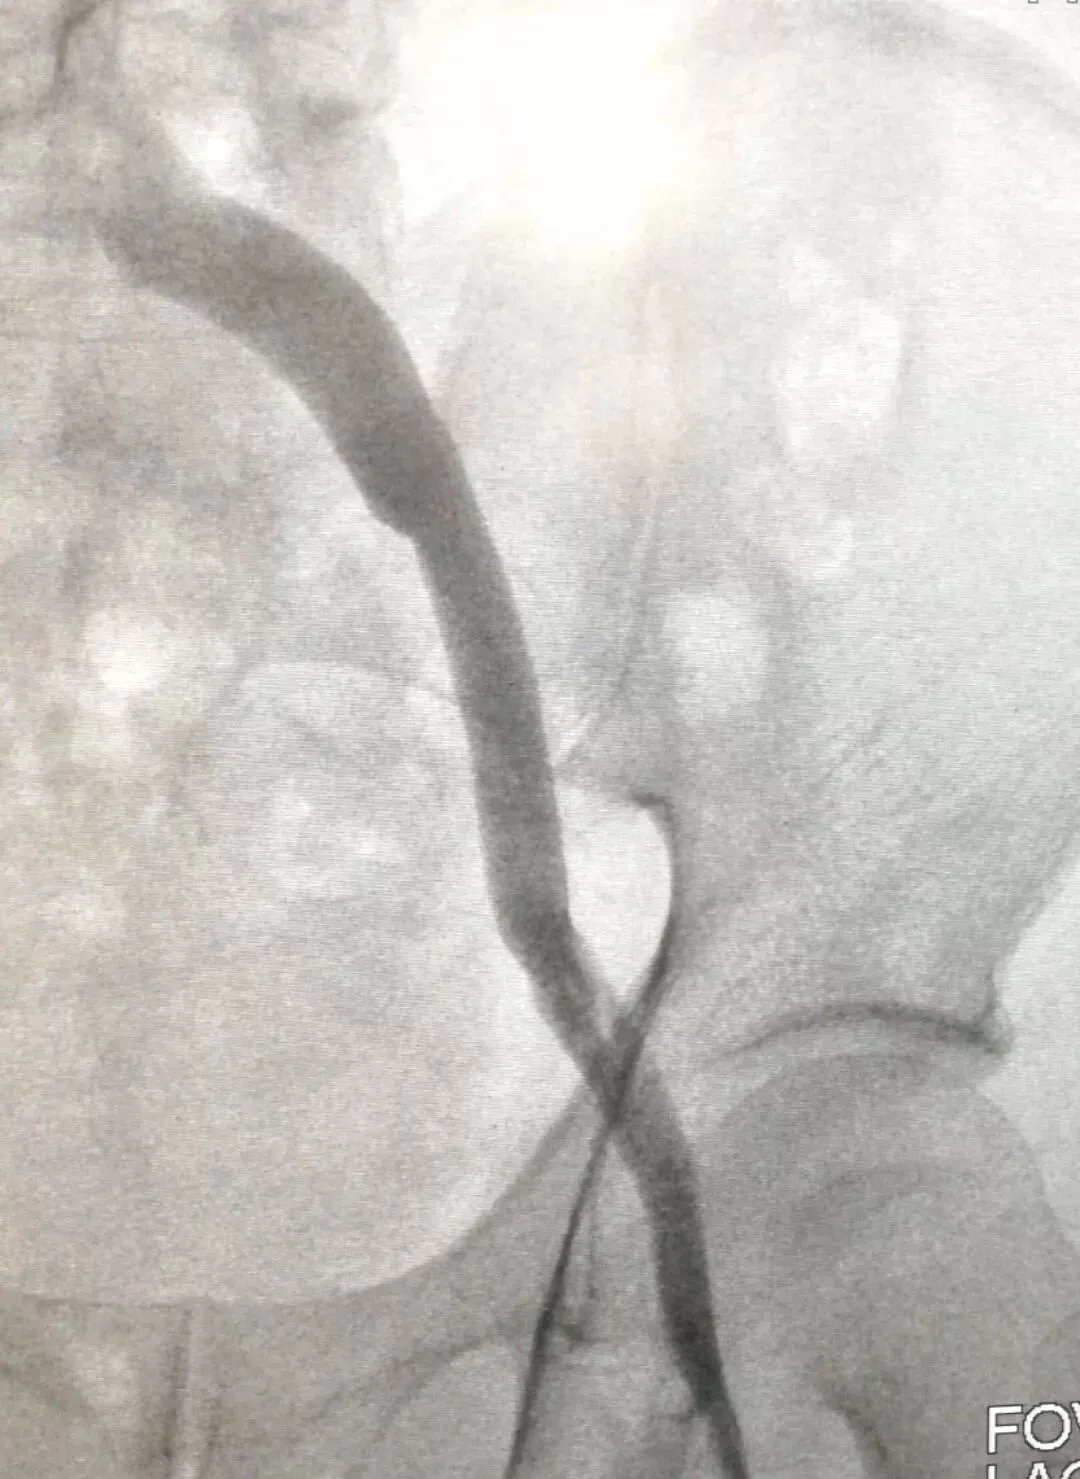

通过下图DSA造影可以看到,治疗前,血管几乎被完全堵塞;治疗后,血管通畅。

治疗前

治疗后

(治疗前后对比)